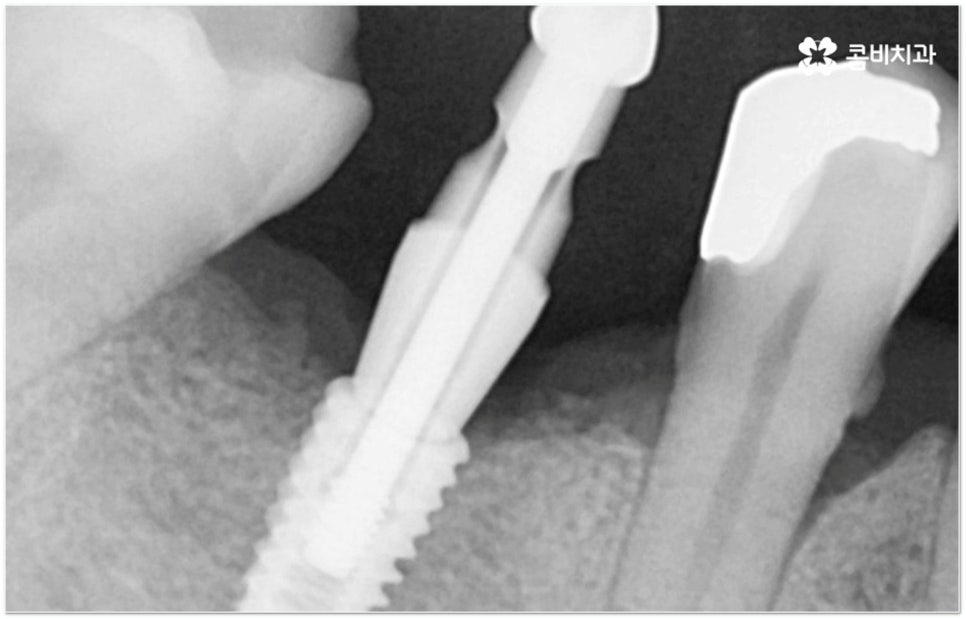

그러나 임플란트는 잇몸뼈에 직접 심어서 고정시키는 방식인 만큼 만약 환자분의 잇몸뼈가 부족하거나 치아가 빠진 후 오랜 시간이 지나 이미 잇몸뼈 소실이 상당 부분 이루어진 상태라고 한다면 먼저 골이식을 통해 이를 보충한 후 식립을 진행하는 뼈이식임플란트 방식을 이용할 필요가 있어요. 골이식 과정은 바탕이 되는 잇몸뼈의 밀도나 높이, 두께가 부족한 부분에 이식 재료를 심어주어 뼈를 재건해 주는 것인데 충분한 시간을 두고 무리하지 않게 진행하는 것이 뼈이식임플란트 수술의 성공률 및 안정적인 지속성을 높일 수 있는 방법이 될 거예요.

다양한 이식 재료는 각각 장단점을 가지고 있기 때문에 꼼꼼한 검진 및 상담을 통해 환자분들의 상황에 맞게 필요한 골이식재의 양과 비율을 조절해 주는 것이 중요하다고 할 수 있는데요. 예를 들어 이식재 중 자가골의 경우 본인의 뼈를 활용하는 것이기 때문에 감염의 위험이 낮고 직접 골아세포에 의한 골형성을 할 수 있어 빠른 골융합을 기대할 수 있으므로 신생골이 필요한 부위에 쓰면 좋으나 많은 양을 채취하기 어려운 만큼 골이식 범위가 넓거나 골이식 해야 하는 치아 개수가 많을 경우 신체 다른 부위에서 떼어내는 외과적인 수술이 병행되어야 하거나 다른 재료(동종골, 이종골, 합성골 등)와 함께 사용할 필요가 있어요. 동종골은 같은 사람의 뼈라는 점에서 골형성에 기여하는 골유도 기능을 할 수 있으나 가격이 비싸고, 이종골은 골형성시 흡수가 느리기 때문에 뼈대를 만들어주고 공간 유지를 해 주는 골전도 능력이 우수하여 새로운 뼈가 채워지는데 오래 걸리지만 자가골이나 동종골보다는 구하기가 쉽기 때문에 가장 많이 사용하는 재료이며 합성골 역시 뼈를 만들어내는 효율은 떨어지지만 비용이 저렴하기 때문에 다른 골이식재와 혼합하여 사용할 때 서로 보완이 될 수 있습니다.

뼈이식임플란트 가 필요한지 살펴볼 때 3D CT 촬영과 같은 정밀 진단을 통해서 환자분의 잇몸뼈 두께 등 치조골 상태 뿐 만 아니라 구강 구조, 치아 및 잇몸 상태, 신경관 위치, 상악동까지의 거리 등을 꼼꼼하게 확인하여 치료 계획을 세우고 필요하다면 구강 질환에 대한 치료나 상악동 거상술 등을 선행하며 잇몸뼈 부족에 대해서도 골이식 과정을 먼저 진행하게 되는데요, 이러한 뼈이식임플란트 시술은 상당히 고난도의 복잡한 치과 진료인 만큼 관련 임상 경험이 풍부한 의료진과 함께 하는 것이 굉장히 중요하며 또한 수술 후 관리 면에서도 더욱 신경을 써 주시길 당부드리고 있어요.